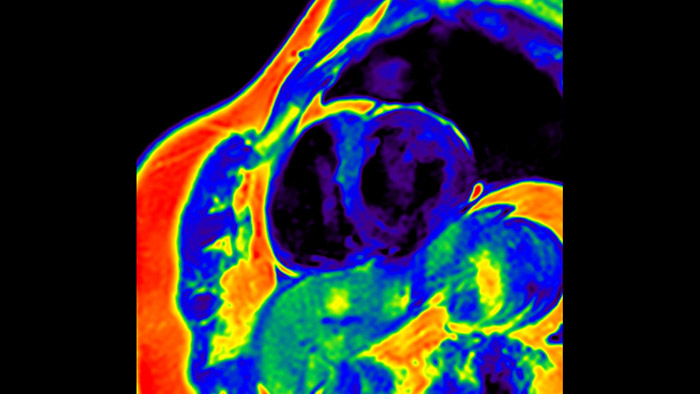

Diagnostic and prognostic utility of cardiac MR is increasing. Assess the anatomy and function of the heart using cine acquisitions, acquire information about perfusion and viability of the cardiac tissue, visualise potential edema with black blood sequence, access and even quantify tissue characterisation with CardiacQuant.

IntelliSpace Portal MR Caas5,6 4D Flow post-processing solution enables generation of 3D volume reconstructions, to visualise and evaluate blood flow in cardiovascular structures, including heart valves, chambers, and vessels, based on cardiovascular MR 4D Flow imaging.

IntelliSpace Portal MR Caas5,6 Strain7 assists in patient diagnosis and monitoring by providing global strain parameters such as global longitudinal strain (GLS), global circumferential strain (GCS), and global radial strain (GRS), using short and long axis MR images, as well as describing the myocardium deformation- such as shortening, thickening, and lengthening during the cardiac cycle.